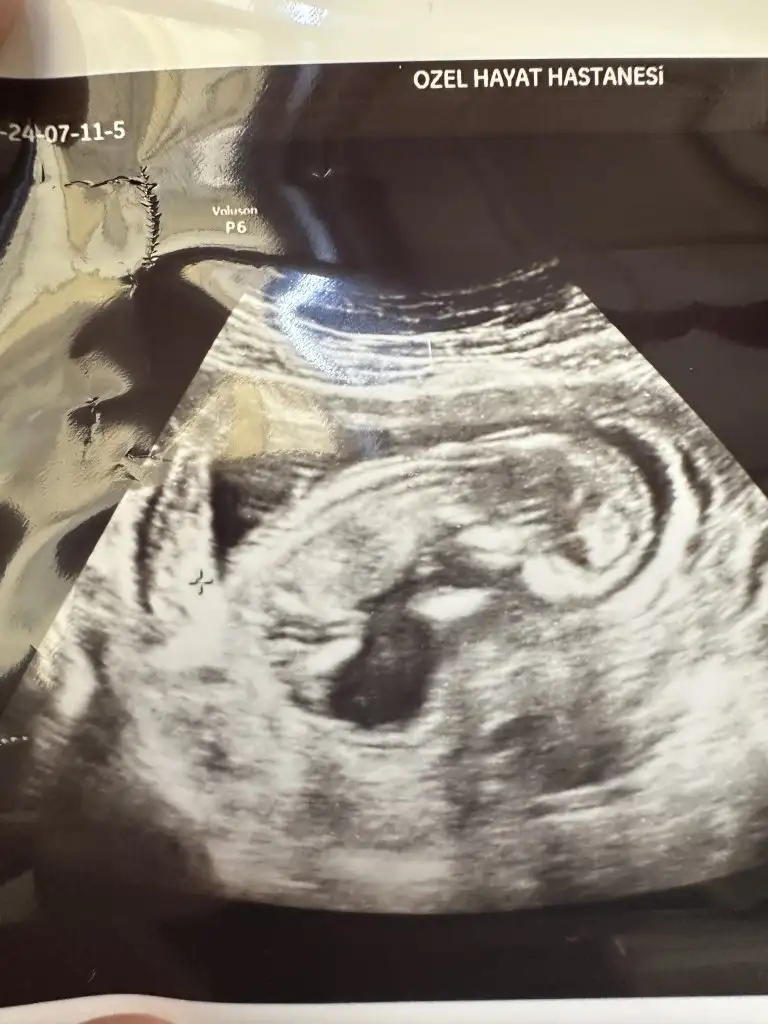

12 haftalık cinsiyeti belli oldu

Merhaba biz de 12 haftalığız ultrason resim çok benzettim benim bebeğime bize doktor yanılma payım yüksek emin değilim sadece tahmin kıza benziyor dedi sizce bakar mısınız kız mı erkek mi bana hiç kız gibi gelmiyor erkek gibi geliyor

Doktor bacak arası resim verdi sizce nedir cinsiyeti

Kızlar dün doktorum cinsiyet tahmini yaptı kız büyük ihtimal ama 3 hafta sonra tekrar bakarız kesin o zaman belli olur dedi ben hep erkek hissediyordum ama kız olunca çok mutlu oldum hissiyat olarak sadece erkek olucak kesin diyordum ama yanıldım sanırım sizce cinsiyeti değişicek mi çok heycanlıyım ☺️ Ultrason fotoğrafını asağıya ekliyorum Eki Görüntüle 3233482